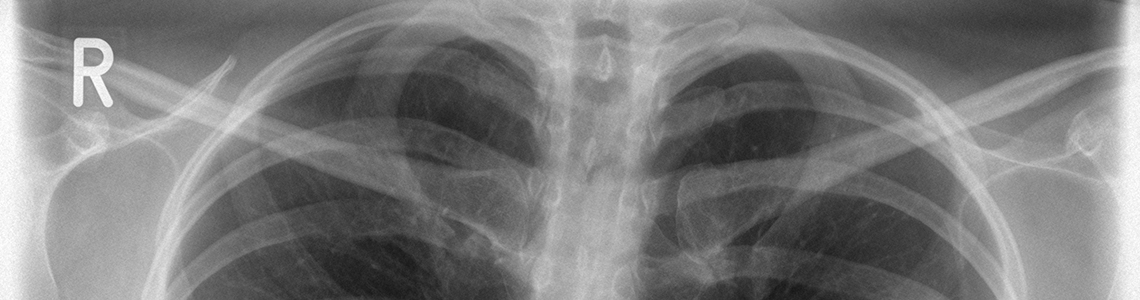

Die Röngtenstrahlen, energiereiche elektromagnetische Wellen, durchdringen bei der Untersuchung den Körper und werden dabei, je nach Gewebeart, unterschiedlich stark abgeschwächt. Knochengewebe beispielsweise führt zu einer starken Abschwächung, während zum Beispiel die Lunge von den Strahlen fast ungeschwächt passiert wird.

Die Röntgenuntersuchung ist auch heute noch die Erstuntersuchung bei Verdacht auf einen Knochenbruch und bei Erkrankungen der Lunge (z.B. bei V.a. Lungenentzündung)

- alle Standarduntersuchungen des Schädels, der Wirbelsäule, der Gelenke und Knochen sowie der Lunge